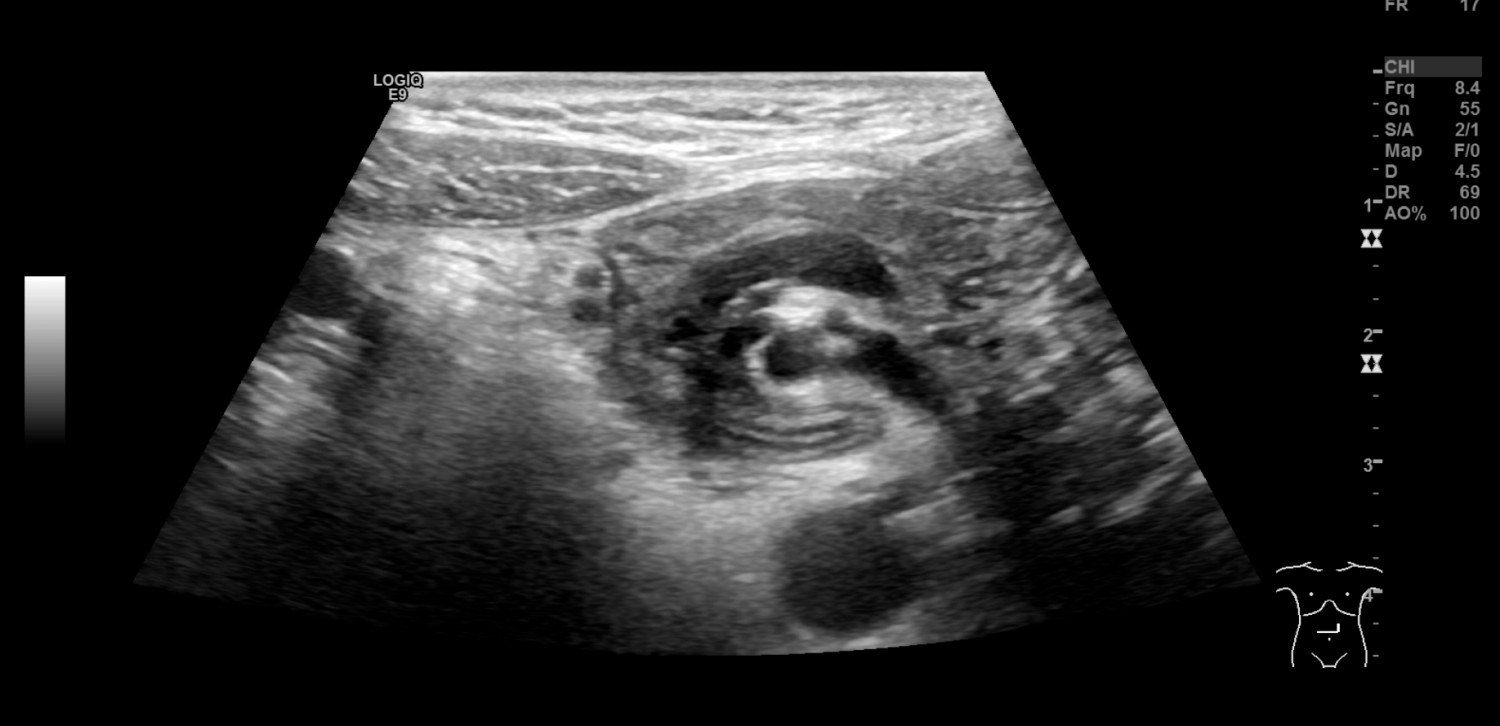

En såpass uttalt og akutt forverring passet ikke med tidligere vurderte diagnoser som abdominal migrene, gastroøsofageal refluks eller obstipasjon, og differensialdiagnostisk ble ventrikkelretensjon eller arteria mesenterica superior-syndrom vurdert. Ved innkomst startet man behandling med erytromycin (Ery-Max) mikstur 3 mg/kg for å stimulere til ventrikkeltømming, intravenøs NaCl og glukoseløsning tilsatt natrium og kalium, samt kaliummikstur 10 ml x 3 peroralt. Ultralyd abdomen ble utført av radiologisk lege i spesialisering fredag kveld, og det ble beskrevet virvellignende rotasjon (whirl sign) i epigastriet som involverte vena og arteria mesenterica superior (figur 1). Legen mistenkte intestinal malrotasjon og anbefalte i første omgang kontrollultralyd av erfaren barneradiolog på dagtid. Det ble også bemerket spiss vinkel mellom aorta og proksimale del av a. mesenterica superior, som ved mulig arteria mesenterica superior-syndrom. Det var normale funn ved røntgen oversikt abdomen.

Gjennom helgen ble jenta observert. Hun hadde bedre allmenntilstand, lite magesmerter og ingen episoder med oppkast. Elektrolyttnivået ble raskt normalisert etter påbegynt væskebehandling. Mandag formiddag ble det gjort ultralydkontroll av en erfaren barneradiolog som bekreftet funn av virvellignende rotasjon (figur 1 og 2) og som mistenkte ledsagende volvulus (tarmslyng som følge av at et tarmsegment vris rundt sin egen akse). Diagnosen ble bekreftet med røntgen øsofagus, ventrikkel og duodenum som viste kontrastpassasje til proksimale tynntarm, men ikke videre (figur 3). Overgangen mellom duodenum og tynntarm lå like til venstre for midtlinjen, kaudalt for nivå med bulbus duodeni, noe som indikerte malrotasjon med volvulus. Man hadde omsider funnet forklaringen på pasientens langvarige plager (figur 4).

Ved ultralydundersøkelse ligger normalt v. mesenterica superior til høyre for a. mesenterica superior. Hvis venen ligger til venstre eller foran arterien, gir det sterk mistanke om malrotasjon. Sensitivitet er angitt til 67–100 % og spesifisitet til 83–92 % (7). Ved unormalt leie påvist på ultralyd bør man gå videre med røntgen av øsofagus, ventrikkel og duodenum. Hos vår pasient så man på ultralyd det såkalte «whirl sign», som er regnet som 100 % spesifikt for midttarmsvolvulus (7): Duodenum, proksimale del av tynntarm og v. mesenterica superior snurrer rundt a. mesenterica superior. Bakenforliggende årsak er malrotasjon og et kort mesenterium. Midttarmsvolvulus gir en duodenal, altså en helt proksimal obstruksjon, og røntgen oversikt abdomen kan således vise helt normale funn, mens barnet likevel har en akutt, operasjonstrengende tilstand.